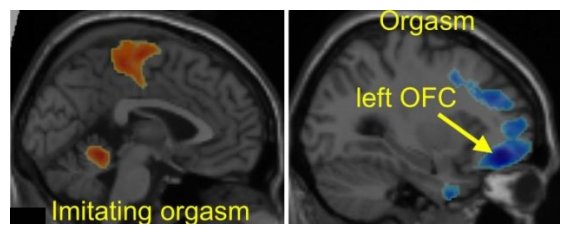

ΠαλαιÏŒτερες μελÎτες Îχουν υποδείξει την περιοχή του εγκεφάλου που ελÎγχει τον oργασμÏŒ. Στα αριστερά, παρουσιάζεται η εγκεφαλική διÎγερση στο συνειδητÏŒ τμήμα του εγκεφάλου (με πορτοκαλί χρÏŽμα). Στα δεξιά, παρουσιάζεται η εγκεφαλική λειτουργία της στιγμή του oργασμοÏ (με μπλε χρÏŽμα), με απενεργοποίηση των κÎντρων του φÏŒβου και των συναισθημάτων.